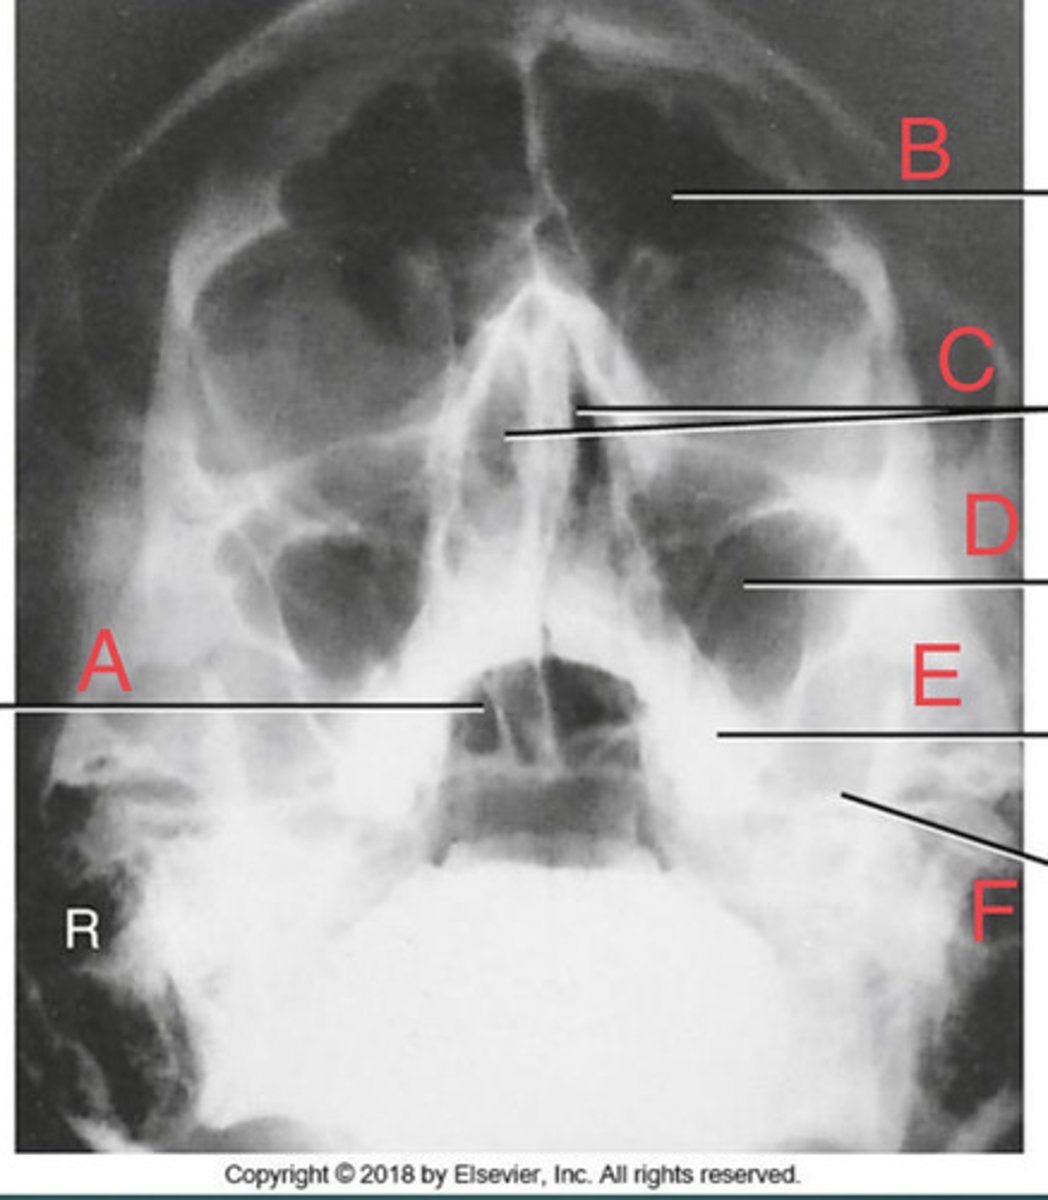

Waters sinus method

What projection?

r. frontal sinus of the frontal bone

A.

R. Maxillary sinus of maxilla

B.

R. petrous ridge of temporal bone

C.

bony nasal septum

D.

L. inferior orbital fissure of sphenoid bone

E.

Sphenoid sinus of sphenoid bone

F.

bony nasal septum

E.